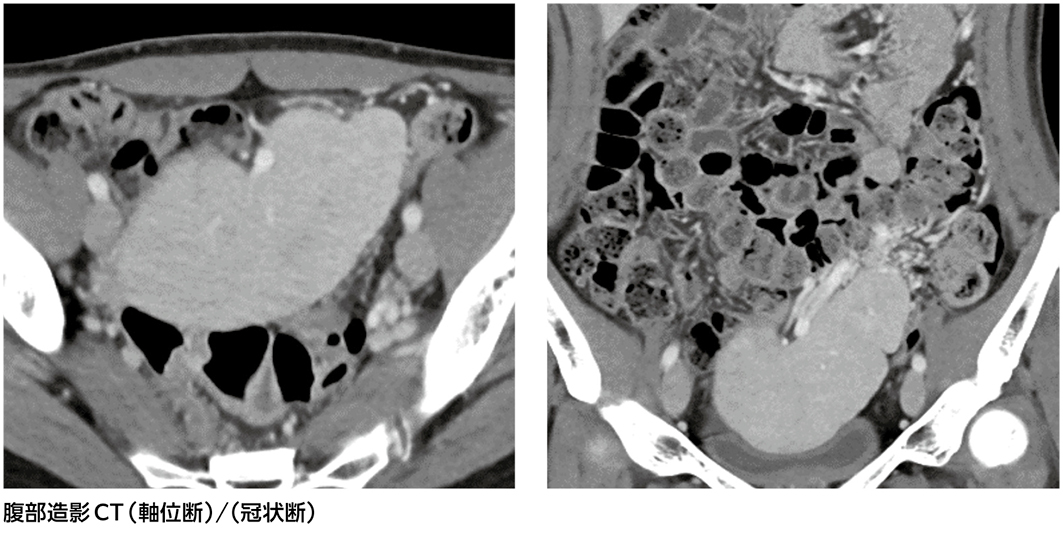

骨盤内腫瘍?それとも……[画像診断道場~実はこうだった(329)]

20歳代,女性。

前医で骨盤内腫瘍を指摘され当院へ紹介受診。

自覚症状なし。半年前から卵巣内膜症性囊胞による月経困難症の治療中。

妊娠出産歴はなく,月経周期は整。内診で強い疼痛あり。採血で特記所見なし。